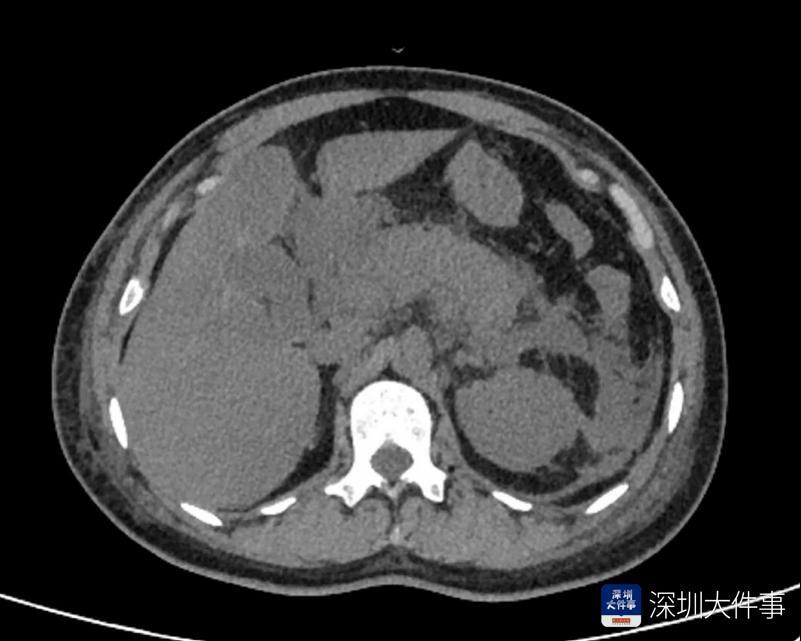

抵达医院时,肖女士已疼得直不起腰,额头渗满冷汗,面色煞白。该院急诊科黄燕医生接诊后,第一时间询问病史并安排抽血、腹部CT等检查。化验结果显示,肖女士血淀粉酶数值达257.2 U/L,脂肪酶数值高达4610.5 U/L,两项指标均远超正常值上限;腹部CT影像则显示其胰腺明显肿胀,周围有脓液渗出,符合急性胰腺炎典型影像学特征,最终确诊为急性胰腺炎。